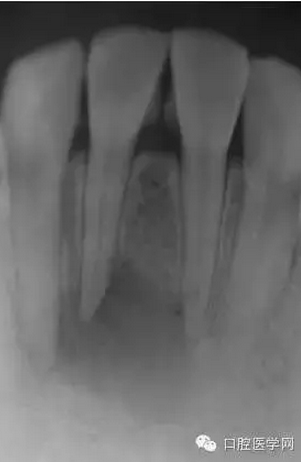

23歲女性患者,下頜右前牙的唇側(cè)有嚴(yán)重腫脹和疼痛。相應(yīng)部位有過(guò)外傷史,但記不起是什么時(shí)候了。放射線照片顯示以右下頜中切牙為中心,有波及右下側(cè)切牙及左下中切牙的大范圍的根尖周病變,臨床檢查時(shí),無(wú)齲壞,只發(fā)現(xiàn)右下中切牙略有變色,牙髓活力檢查(電子牙髓檢查及冷檢查)發(fā)現(xiàn),右下中切牙無(wú)反應(yīng),而鄰近齒表現(xiàn)為正常。判斷大范圍的根尖周病變的原因是受過(guò)外傷的右下中切牙的牙髓壞死,受周邊環(huán)境影響,發(fā)展為急性根尖周膿腫。

(圖 1) 初診的放射線照片